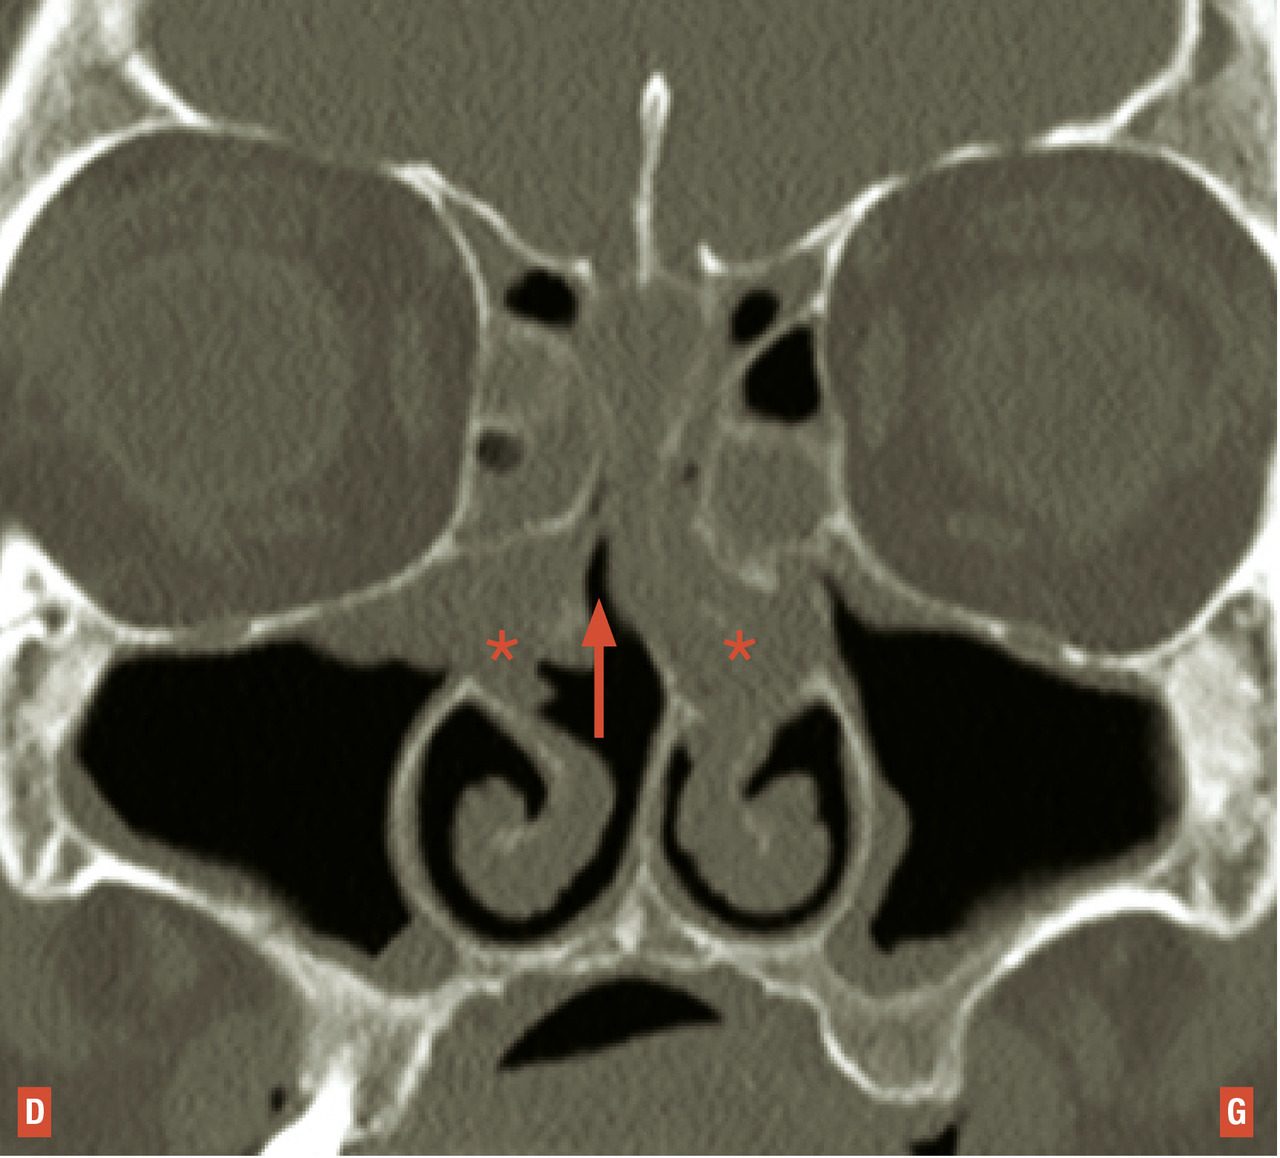

Le dysfonctionnement nasal chronique d’une allergie aux acariens peut se rapprocher de celui d’une rhinite non allergique à éosinophiles ou d’une polypose nasale mais la fibroscopie nasale ne trouve pas de polypes francs des méats moyens ou des fentes olfactives. Elle objective seulement un aspect œdémateux, parfois même pseudo- polypoïde, de la tête ou du bord libre des cornets moyens, associé à une hypertrophie blanche, rouge ou lilas des cornets inférieurs, par ailleurs tapissés de sécrétions séreuses ou muqueuses qui peuvent s’accumuler sur le plancher nasal. Une tomodensitométrie doit alors compléter la démarche diagnostique. Dans la rhinite chronique aux acariens, les masses latérales de l’ethmoïde et les sinus paranasaux montrent une radiotransparence normale alors que l’essentiel des signes pathologiques sont retrouvés au niveau du nez respiratoire (qui ne fait actuellement l’objet d’aucune description dans les comptes-rendus radiologiques) [fig. 2 ]. C’est donc la concordance des signes nasofibroscopiques et tomodensitométriques qui contribue au diagnostic des rhinites respiratoires chroniques. L’origine allergique, toujours recherchée, n’est cependant pas systématiquement retrouvée.7

Le dysfonctionnement nasal chronique d’une allergie aux acariens peut se rapprocher de celui d’une rhinite non allergique à éosinophiles ou d’une polypose nasale mais la fibroscopie nasale ne trouve pas de polypes francs des méats moyens ou des fentes olfactives. Elle objective seulement un aspect œdémateux, parfois même pseudo- polypoïde, de la tête ou du bord libre des cornets moyens, associé à une hypertrophie blanche, rouge ou lilas des cornets inférieurs, par ailleurs tapissés de sécrétions séreuses ou muqueuses qui peuvent s’accumuler sur le plancher nasal. Une tomodensitométrie doit alors compléter la démarche diagnostique. Dans la rhinite chronique aux acariens, les masses latérales de l’ethmoïde et les sinus paranasaux montrent une radiotransparence normale alors que l’essentiel des signes pathologiques sont retrouvés au niveau du nez respiratoire (qui ne fait actuellement l’objet d’aucune description dans les comptes-rendus radiologiques) [

L’obstruction nasale chronique liée à un dysfonctionnement mécanique des plexus caverneux du nez respiratoire est typiquement à bascule ou majorée par le décubitus. Elle peut gêner le sommeil et aussi être sévère durant la journée, gênant l’élocution (rhinolalie fermée), l’alimentation, les activités physiques (dyspnée d’effort). La fibroscopie nasale peut montrer une hypertrophie non inflammatoire des cornets inférieurs sans aspect pathologique du bord libre des cornets moyens ou être normale au moment de l’examen, et note fréquemment une déviation septale associée. La tomodensitométrie du nez et des sinus montre chez ces patients une radiotransparence normale des cavités nasales et sinusiennes*, elle peut montrer une déformation septale, le cas échéant, et parfois une hypertrophie turbinale inférieure. Le dysfonctionnement nasal chronique de ces patients n’a pas de support inflammatoire et ne mérite pas un bilan causal de rhinite ou de rhinosinusite chronique.